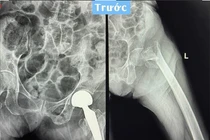

hoai-tu.png

Hình ảnh khớp phải trước và sau phẫu thuật - Ảnh BVCC

Ca phẫu thuật do BSCKII Vũ Quang Nghĩa, Trưởng Khoa Chấn thương chỉnh hình Bệnh viện Bãi Cháy thực hiện đã thành cắt bỏ tổn thương hoại tử, thay khớp háng bằng vật liệu nhân tạo phù hợp. Sau phẫu thuật 3 ngày, bệnh nhân phục hồi vận động tốt, có thể tập đi lại cùng dụng cụ tập.